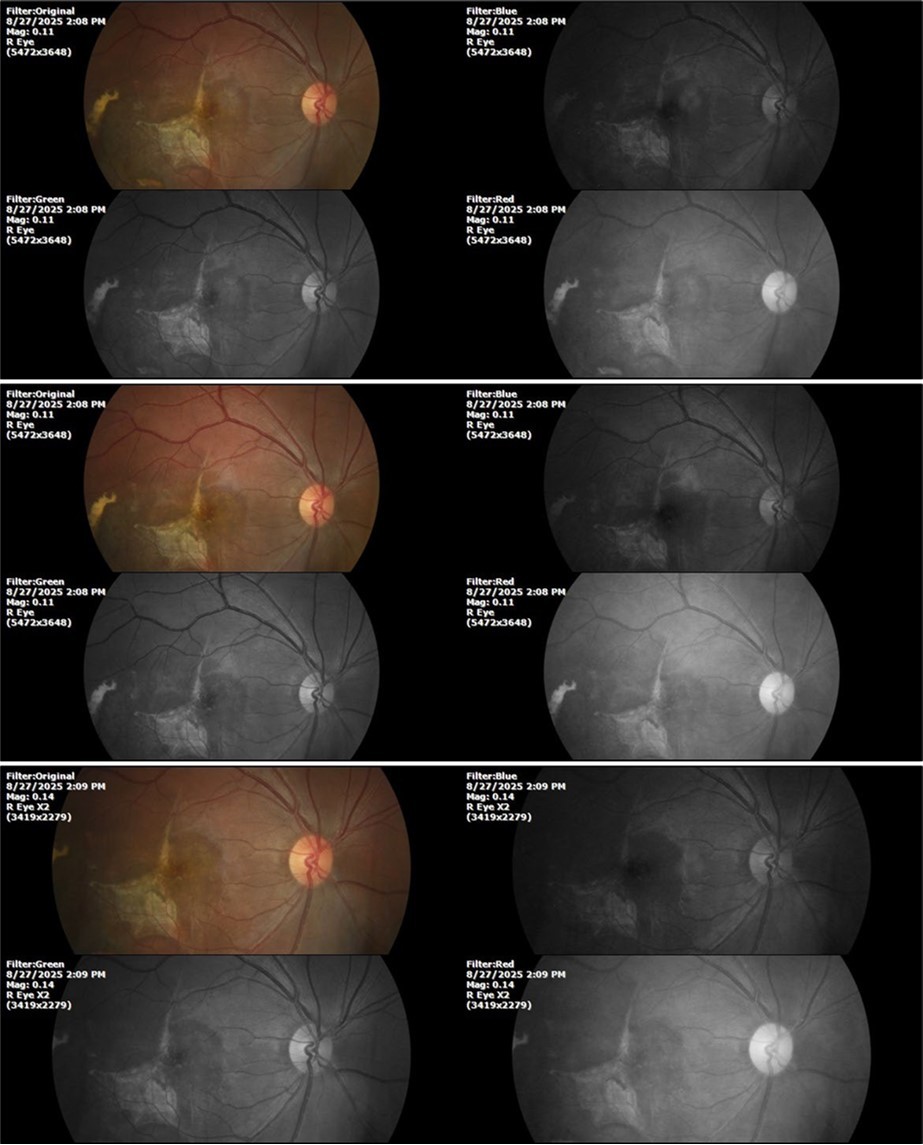

Figure 8.The photograph of the superior temporal region of the retina of the right eye shows the extent of subretinal bleeding as well as retinal edema.

Figure 9.The extent of bleeding, mainly subretinal, is extensive and of significant volume, suggesting choroid rupture in this area.

Figure 10.The location of the bleeding is mainly subretinal, although blood is seen in minimal quantity in the vitreous body.

Figure 27.The three previous photographs of the right fundus show that the whitish mass composed mainly of phantom cells continues to decrease.

Figure 33.The 3 previous photographs show that whitish mass has almost completely disappeared, and to date only a remnant remains on the left side of the photograph. The chorioretinal scar that is now observed corresponds to the area affected by the blunt trauma, which presumably caused rupture of Bruch's membrane. Fortunately, the macular region has recovered almost in its entirety, so the impairment in central vision was minimal.